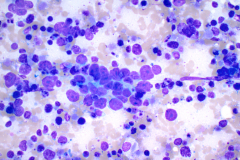

BSCC reportedly display very high nuclear/cytoplasmic ratio with coarse chromatin, inconspicuous to prominent nucleoli and nuclear pleomorphism. The nuclei also mold, and the cells tend to arrange in cohesive clusters, with necrosis in the background.6 This case demonstrates all these criteria (see figures 1-4).